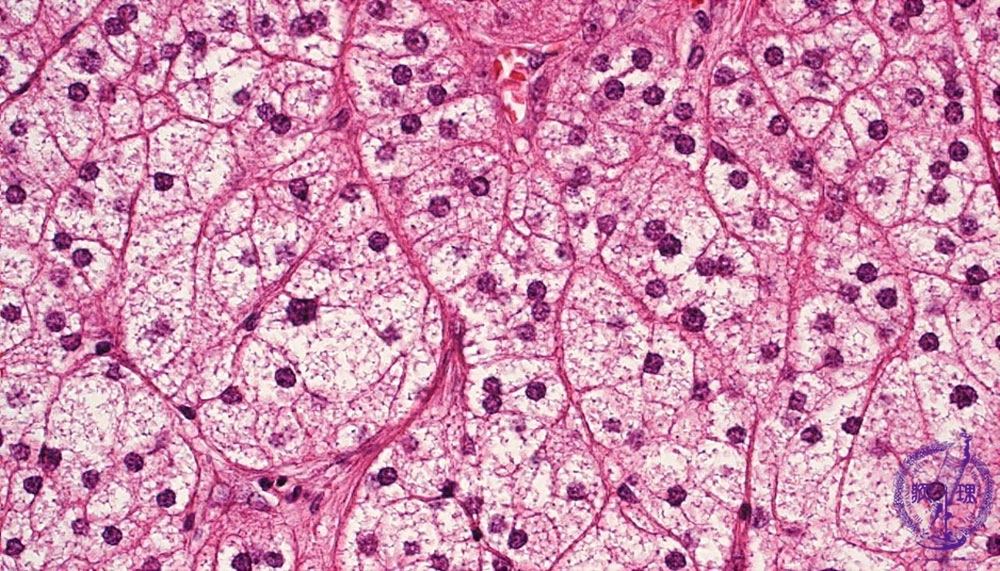

• š(13)Adrenocortical adenoma (Cushing syndrome)

Microscopic findings (HE stain, high power view). Clear cells with lipid-rich foamy cytoplasm. These tumor cells are similar to the cells of zona glomerulosa in adrenal cortex.